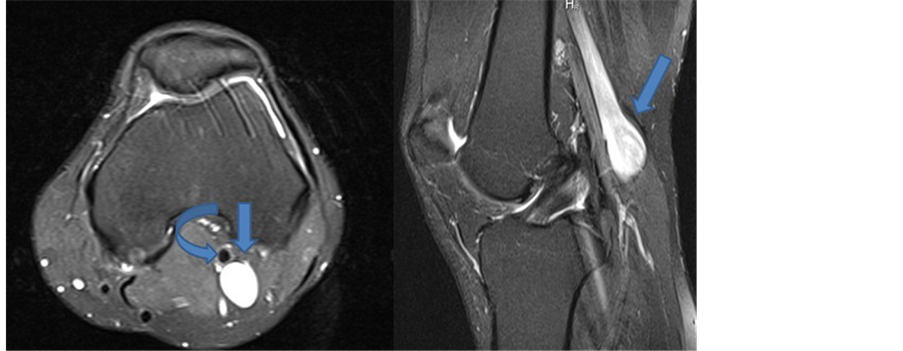

which was milder and denied any history or signs related to severe complications of PVAs such as deep vein thrombosis or pulmonary emboli. We performed duplex ultrasonography once again plus magnetic resonance imaging (MRI) which this time revealed an AP diameter of 19milimiters in the left popliteal vein (Figure 3).

Figure 3. Axial and sagittal fat suppresed proton density MRI images demonstrates left popliteal aneurysm (arrows) posterior to popliteal artery (curved arrow).